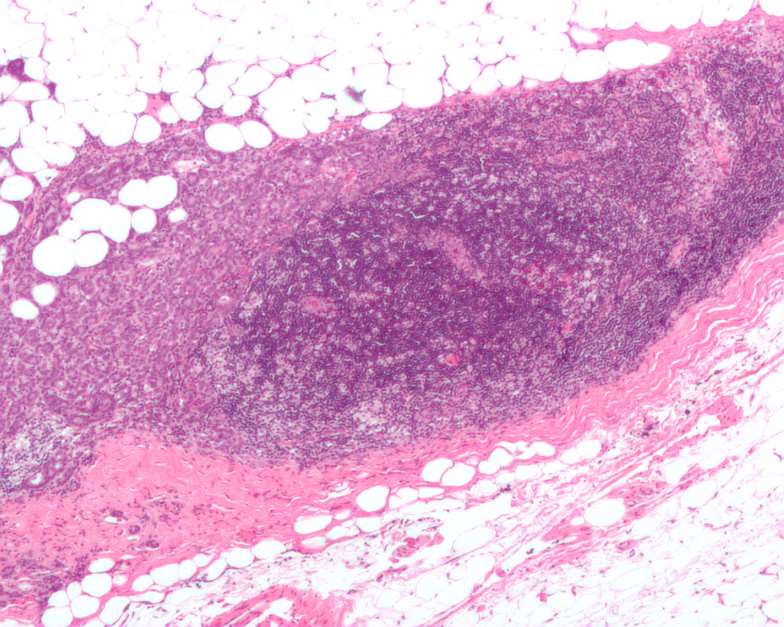

Micrografía que muestra un ganglio linfático invadido por un carcinoma de mama ductal. Foto: Wikipedia